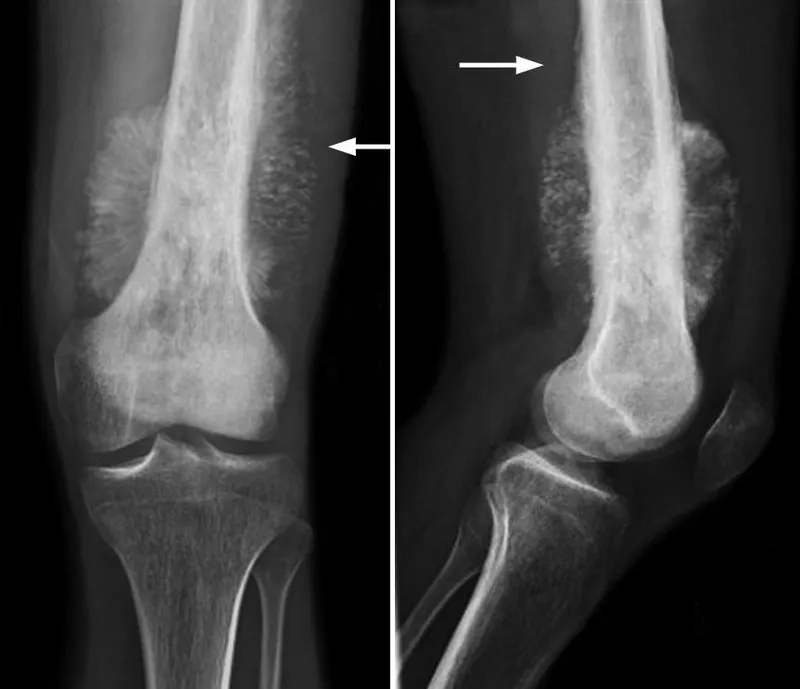

⭐ The classic X-ray findings are a "sunburst" pattern and Codman's triangle.

- X-Ray Findings (Classic Triad):

- Sunburst appearance: Spiculated periosteal reaction.

- Codman's triangle: Triangular elevation of the periosteum.

- Destructive, ill-defined mixed lytic & sclerotic lesion.

- Classic X-ray findings include Codman's triangle and a "sunburst" pattern.